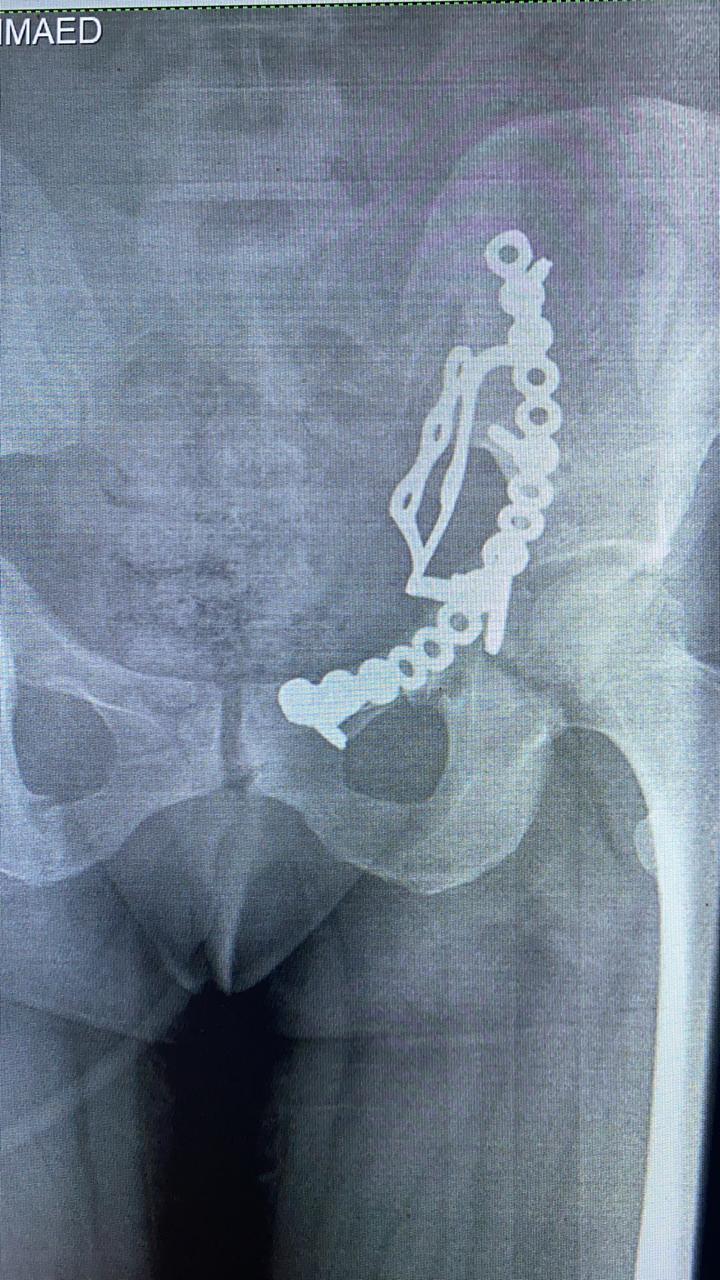

إجراء عملية إصلاح كسور متعددة مفتتة بالحوض لأول مرة بالشرقية

قال الدكتور هشام شوقي مسعود، وكيل وزارة الصحة بمحافظة الشرقية، إن الفريق الطبي بقسم جراحة العظام بمستشفى أبو حماد المركزي، أجرى عملية إصلاح كسور متعددة مفتتة بعظام الحوض لـ سيدة، وذلك للمرة الأولى.

وأوضح وكيل الوزارة، في بيانٍ له، قبل قليل، أنه تم إجراء عملية إصلاح الكسور المتعددة المفتتة بعظام الحوض للسيدة تحت إشراف مدير مستشفى أبو حماد المركزي، إذ تم إجراء عملية رد مفتوح مع تثبيت داخلي لكسر مفتت بالحق الحرقفي لـ عظم الحوض للسيدة، وذلك من خلال جراحة فتح البطن والحوض باستخدام شريحة من نوع خاص تحت مُخدر عام بغرفة العمليات بمستشفى أبو حماد المركزي.

وأشار وكيل وزارة الصحة بمحافظة الشرقية، إلى أن العملية التي أجريت تُعد ذات طابع خاص، وذلك بعد دخول المريضة قسم الاستقبال والطوارئ بمستشفى أبو حماد المركزي، إثر ادعاء حادث مروري، منوهًا بأنه تم إجراء كافة الفحوصات اللازمة، وتبين إصابة المريضة بجرح بالمثانة نتج عنه بول دموي ووجود كسر مفتت بالحق الحرقفي لعظم الحوض، قبل أن يشير إلى إجراء العملية، وأن المريضة الآن في حالة جيدة ومستقرة تحت متابعة الأطباء بمستشفى أبو حماد المركزي.